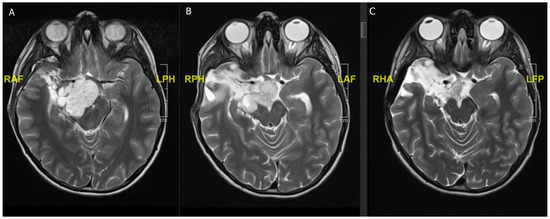

Figure 1. A 21-year-old male, presenting with a generalized seizure. (A) Flair hyperintense fronto-temporal tumor of 8.6 × 4.5 × 5 cm with central hypointensity suggestive of aLGG. (B) T1 hypointense tumor surrounded by the vessels of the sylvian fissure. (C) Postoperative imaging after awake fronto-temporal craniotomy and partial tumor resection due to language impairment intraoperatively.

2. Histology and Anatomical Location

In both children and adults, the mainstay of therapy is surgical resection. Since most patients present with symptoms due to mass effect over the course of several months, the primary goal of therapy is volume reduction [5]. Surgery is the most effective treatment to achieve a volume reduction of the tumor, whilst a histopathological diagnosis can also be reached. In fact, for pLGG, a gross total resection (GTR) of the tumor often means the patient is cured of the disease (since most pLGGs are WHO grade I), while for aLGG (which are mostly WHO grade II), unfortunately, even after GTR, the chances of recurrence and/or malignant transformation remain relatively high [37]. As mentioned above, pLGG and aLGG typically occur at different anatomical locations, which is why the surgical approach and skillset of surgeons differs depending on whether they treat children or adults [6]. Due to the highly eloquent region of the insula, most neurosurgeons treating aLGG are trained in performing awake craniotomies, which are applied in around a third of all insular aLGGs but are rarely applied in children [23,38]. On the other hand, pediatric neurosurgeons often encounter posterior fossa pLGG or exophytic brainstem pLGG and require a specific skillset for these approaches, as well as treating obstructive hydrocephalus or tumor biopsies with endoscopic procedures (e.g., ETV) [39]. Intraventricular tumors (e.g., pLGG within the third ventricle, thalamic pLGG) requiring an endoscopic or transventricular approach, are also more often encountered in children than in adults40 [40]. It is therefore clear that LGGs show anatomical differences in different age groups which directly influences and dictates their treatment strategy. Typically, in children, posterior fossa syndrome, including cerebellar mutism occurs in approximately a third of patients undergoing infratentorial tumor resection, while this is an extremely rare complication after posterior fossa surgery in adults [41]. Some published reports suggest that children recover faster and better after epilepsy surgery compared to adults, while no clear evidence on this matter exists in tumor surgery [42,43,44,45]. In awake tumor surgery, differences in neurostimulation are observed between children and adults, which is most probably due to the different myelination in the cortical and subcortical tracts between the two age groups, indicating different levels of plasticity/brain development [46].